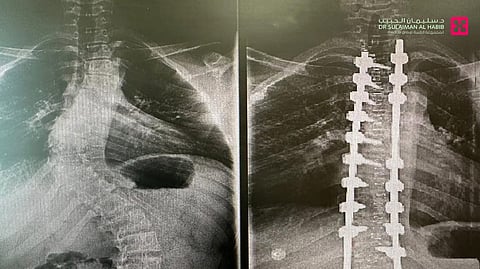

وأضاف أن العملية استغرقت "4" ساعات، وأُجريت تحت المراقبة العصبية الدقيقة، وشملت تصحيح العمود الفقري على امتداد "14" فقرة عبر تثبيتها ودمجها باستخدام أحدث أنظمة التثبيت الجراحي، إضافة إلى إعادة توازن الكتفين وتناسق الخصر، وأسهم في نجاح العملية توفّر أحدث الأجهزة الطبية وكوادر طبية وتمريضية عالية التأهيل.

وبيّن أن المراجع نقل بعد العملية إلى جناح التنويم، وبدأ بالمشي بعد يوم واحد من العملية، وتحسنت حالته مع الرعاية الطبية الحثيثة، وبعد "5" أيام من المتابعة، خرج من المستشفى بصحة جيدة، وقد استعاد قدرته على الجلوس والمشي والنوم بشكل مريح، كما أن طوله زاد بما لا يقل عن "10" سم نتيجة تصحيح الانحناء.